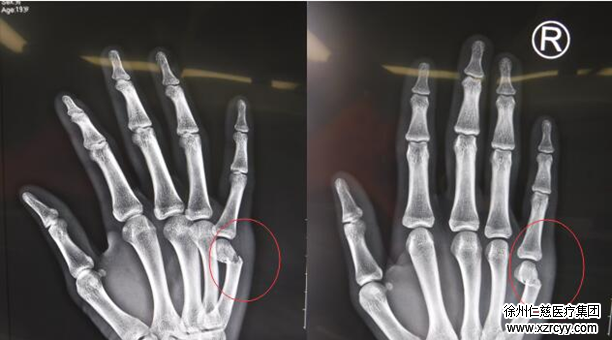

红圈,右手第五掌骨骨折处